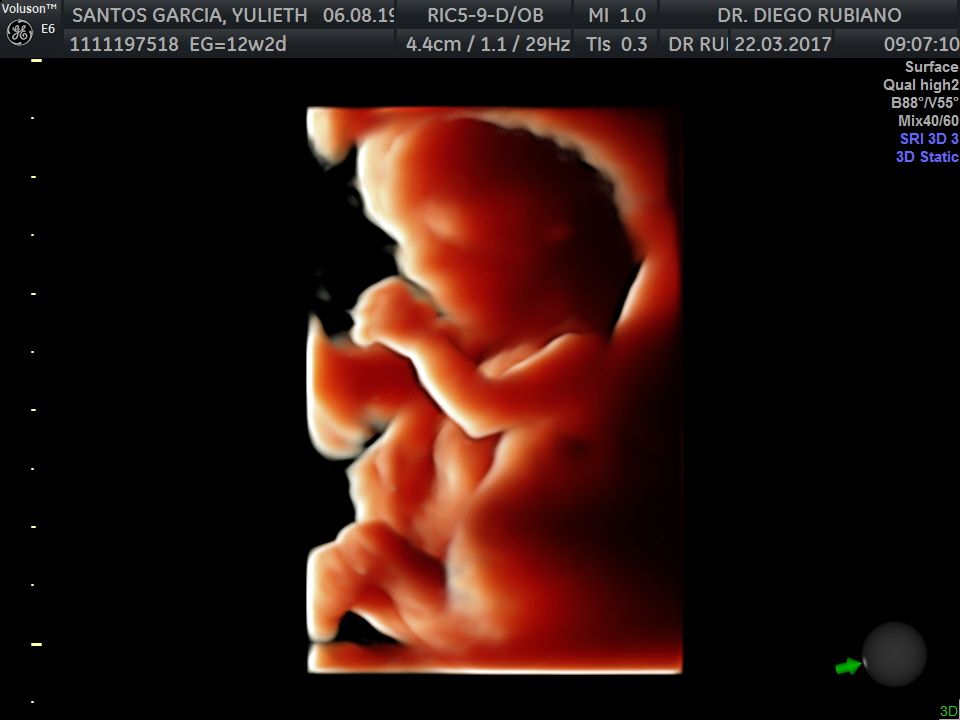

En nuestro consultorio médico, ofrecemos ecografías ginecológicas y obstétricas. Las ecografías ginecológicas son vitales para el control de la salud en mujeres no embarazadas, ayudando a detectar problemas temprano. Para futuras mamás, realizamos ecografías en todas las etapas del embarazo, utilizando equipos de alta tecnología para garantizar un seguimiento preciso del desarrollo del bebé. Ya sea que estés embarazada o no, nuestro servicio de ecografía está diseñado para cuidar de tu salud y bienestar.

• Tamizaje ultrasonografico del primer trimestre (semana 11-14)